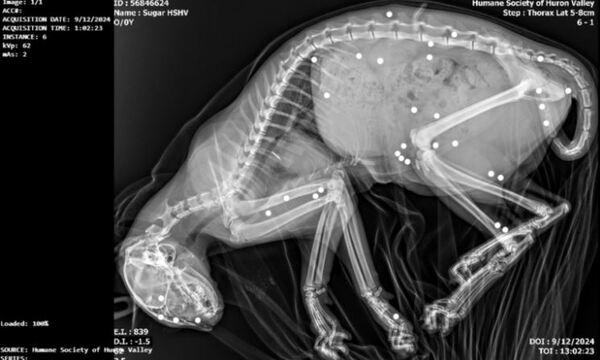

The criminal filing follows the initial public appeal by the Humane Society, which in September 2024 sought the community’s help in identifying those responsible for the violent attack on a 7-month-old kitten found near Carpenter Road and Washtenaw Avenue in Ypsilanti. X-rays revealed approximately 35 BB-gun BBs embedded in the kitten’s body.